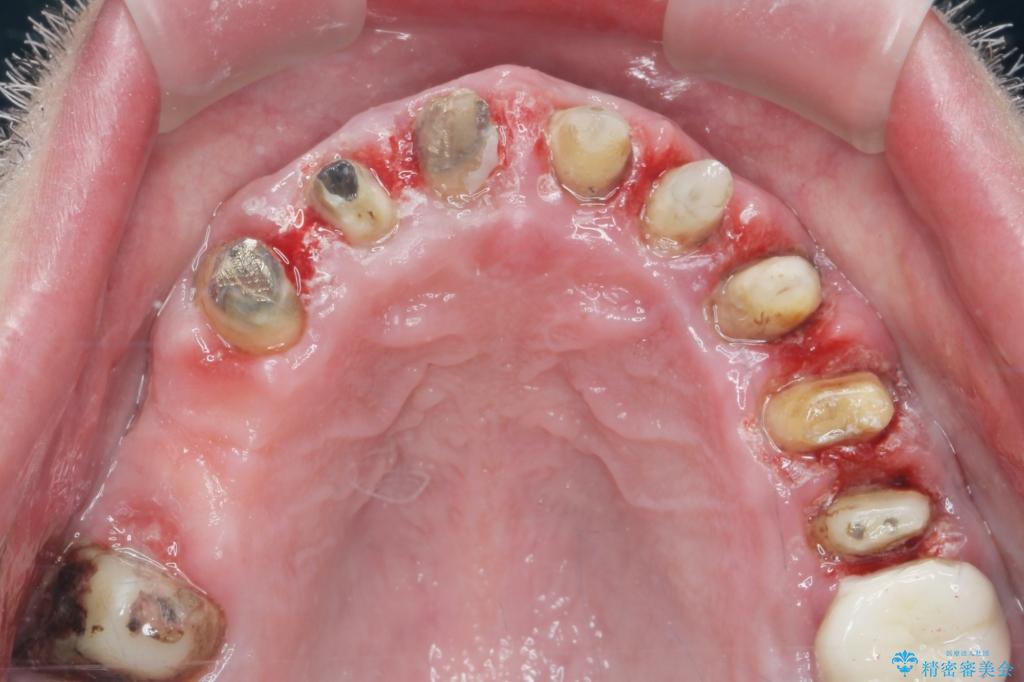

- 「セラミック治療を他院で受けたが、それ以来歯ぐきが腫れ違和感がある、改善してほしい。」と歯ぐきの状態改善を希望され来院されました。

歯周組織検査を行うと歯ぐきからは容易に出血し、X線検査より歯とセラミッククラウンの適合が悪い(ピッタリと合っていない)状態が示唆され、歯ぐきの炎症を惹起している状態でした。

セラミッククラウンを除去し仮歯を装着し、歯周外科手術を行い歯ぐきの状態を改善したのち、適合の良いセラミッククラウンを再作製をする治療計画としました。

見た目の良いクラウンが装着されていても、歯ぐきの状態が悪ければ違和感や歯ぐきの腫れ、臭いの元となっていることが多く見られます。